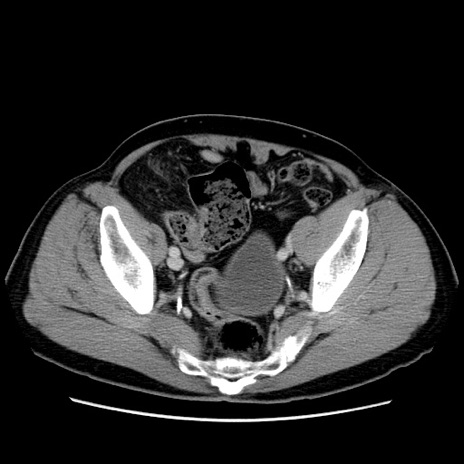

症例34(横断像)

【症例】60歳代 男性

【主訴】右鼠径部膨隆

【現病歴】1年程前より右鼠径部膨隆あり。自己にて還納可能だったため放置していた。3時間前より右鼠径部の脱出を認め、還納困難となり受診。

【既往歴】高血圧

【身体所見】右鼠径部に小児頭大の膨隆あり。弾性硬であり、用手還納は困難。左鼠径部にも膨隆を認める。脱出はなし。